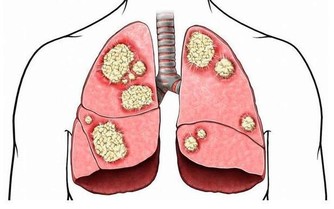

肺怕霧霾、煙氣刺激。中醫學認為,胸中為「上氣海」,丹田為「下氣海」,氣之所以能夠運行於全身,依賴肺氣的推動作用。

肺氣還能貫注於心血管,幫助心臟推動血液運行。

肺為「清虛之髒」,但霧霾、長期吸煙、二手煙不時傷害著它,

導致肺泡內痰飲積滯,阻塞氣道,清氣不能吸入,濁氣不能排出,上下氣海不流通,血液不能正常迴圈。